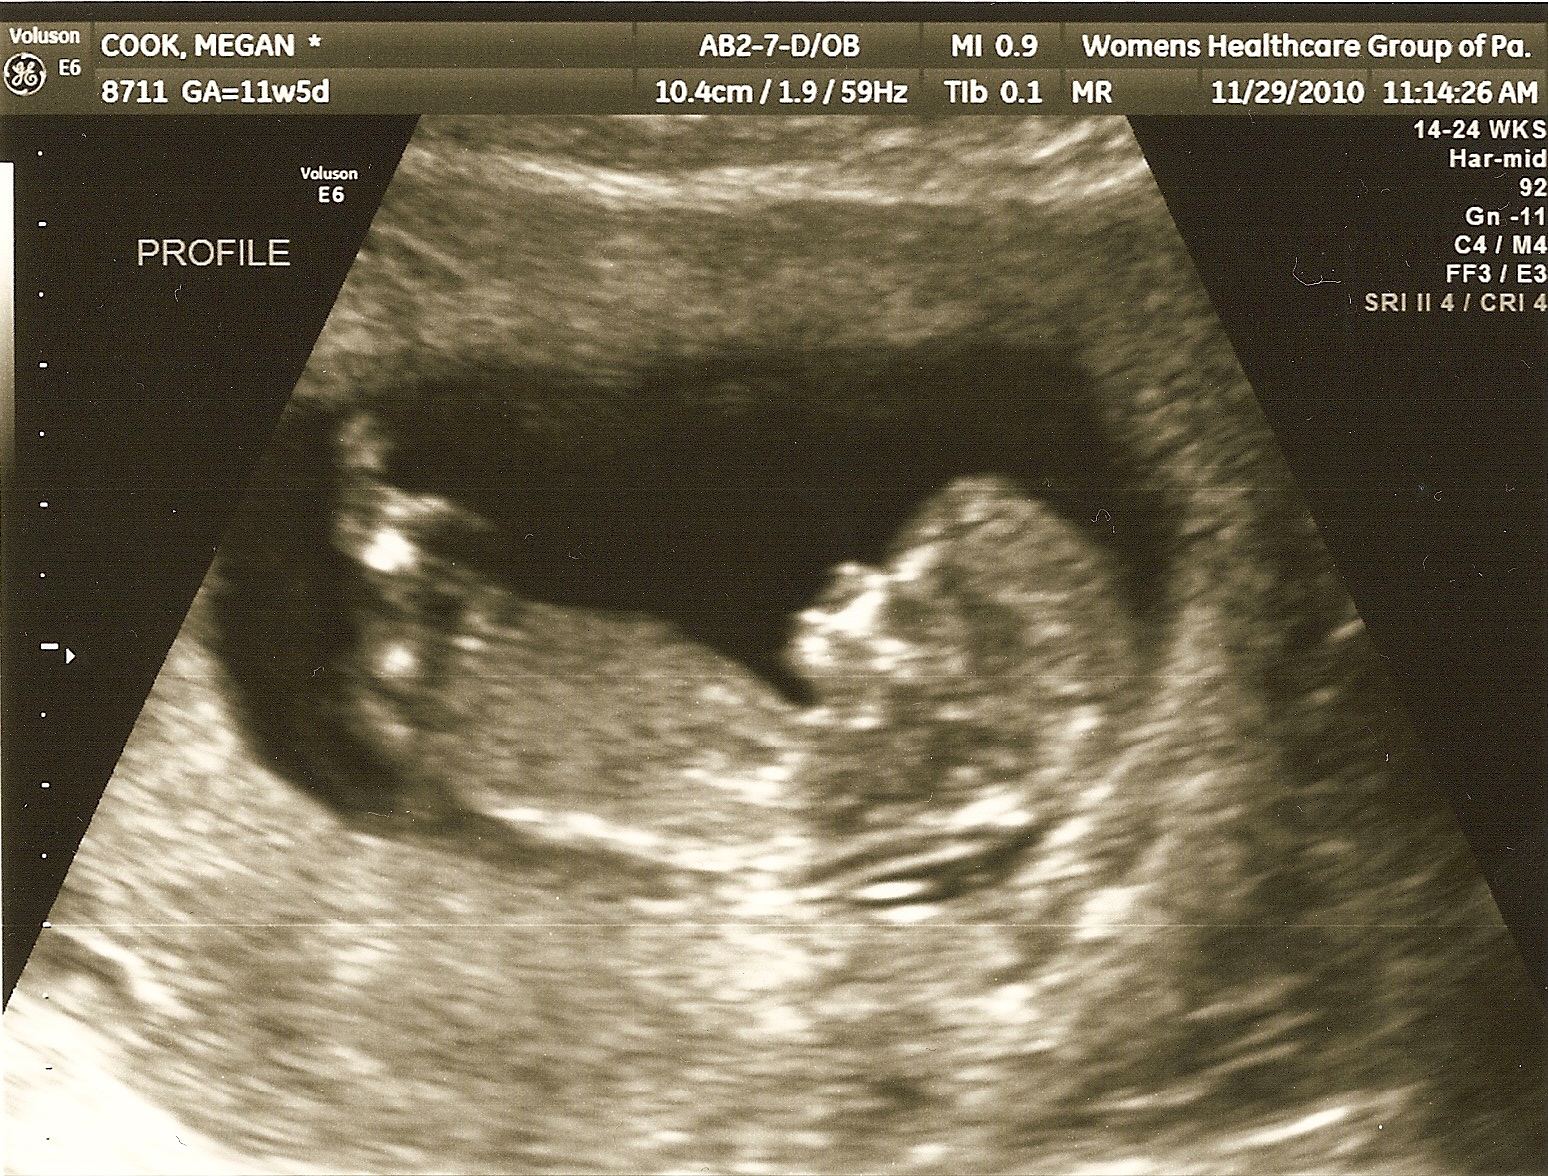

Being that Peanut is only 12 weeks old now we still know very little. What we were told is that Peanut is healthy, has a strong heartbeat, likes to wiggle around a lot ((not that Mommy can feel it!)) and should be arriving around June 13th, 2011.